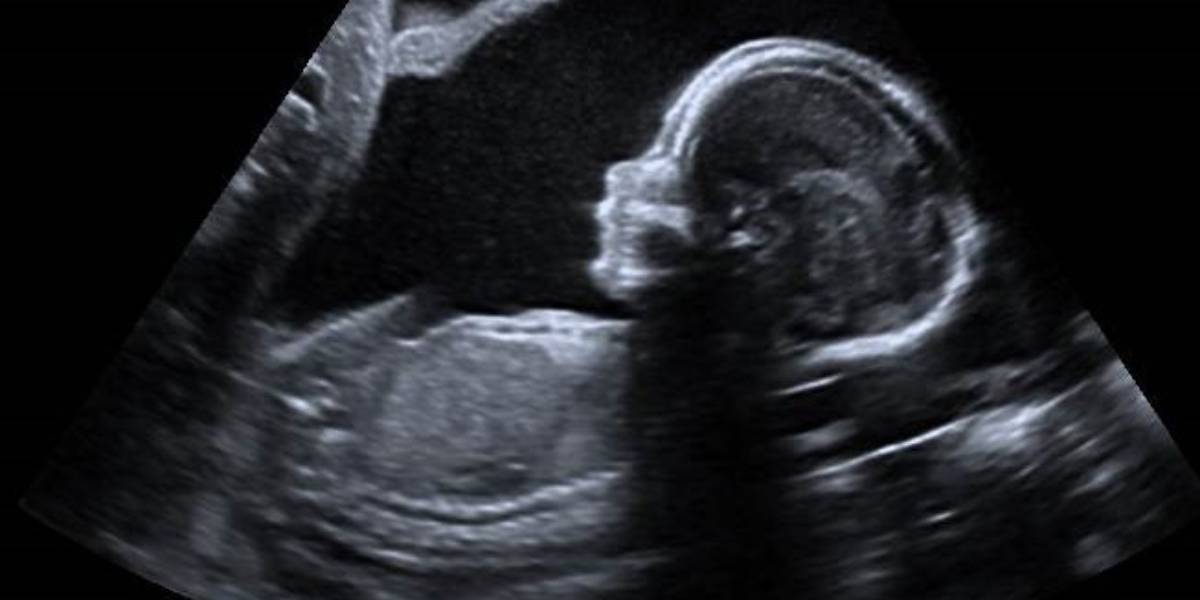

In a case of severe medical negligence, the Kerala State Consumer Disputes Redressal Commission has mandated St. Luke Hospital in Pathanamthitta, along with two gynaecologists, to provide Rs 50 lakh in compensation to a child and their parents. (Creative Commons)

The detection of foetal anomalies — structural, genetic, or functional abnormalities that can affect a developing foetus during pregnancy — is an essential aspect of prenatal care to ensure the health and well-being of both the mother and baby.

This is usually done by the doctors before 20 weeks of gestation so that if there is any abnormality, the foetus can be terminated.

In a case of severe medical negligence, the Kerala State Consumer Disputes Redressal Commission has mandated St Luke Hospital in Pathanamthitta, the district headquarters, along with two gynaecologists, to provide ₹50 lakh in compensation to a child and their parents. This negligence led to the child being born without lower limbs.

Throughout her pregnancy, she underwent multiple ultrasound scans, particularly after the fourth month of gestation.

“Dr Kenny A Thomas had conducted the ultrasound scan, but no hint of such a disaster was brought out through the scanning. Anomaly scan, which ought to have been done during the fourth/fifth months, was not done properly,” said Reshmi Das and her husband in their complaint.

“If a proper anomaly scan was done as stipulated, any abnormality, including congenital diseases to the foetus, could have been detected and if the scanning at the 4th month was properly carried out I could have taken precautionary measures,” their complaint added.

They explained that ultrasound generates a two-dimensional image of a three-dimensional foetus, and as such, it could not provide a 100 percent accurate depiction of the foetus during prenatal testing. The accuracy of ultrasound results depends on factors such as the foetal position and the volume of amniotic fluid.

If amniotic fluid is insufficient or foetal movement is restricted, the sensitivity of ultrasound diagnosis for foetal anomalies may be compromised. In this case, the hospital did not notice any indications of abnormalities during the scanning process.

The commission determined that the standard anomaly scan, critical for identifying foetal abnormalities, was not performed as required and raised two potential scenarios, one suggesting that the reports were issued without actual examination, and the other pointing to carelessness on the part of the second opposite party (the gynaecologist).

The commission relied on the expert opinion of the Head of the Department of Radio Diagnosis at Thiruvananthapuram Government Medical College Hospital, emphasising that anomalies could effectively be assessed during the 18th-week anomaly scan.

The expert clarified that disabilities, if present, could be ascertained at this stage, and the doctor performing the scan should report any anomalies, enabling parents to make decisions regarding the pregnancy.